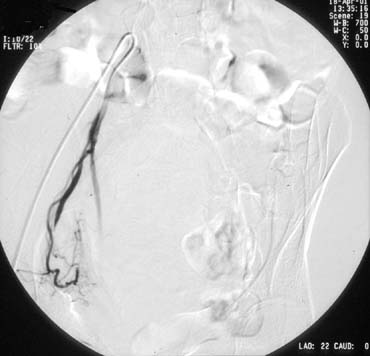

A pelvic arteriogram is generally performed to delineate the arterial anatomy. Embolization of the uterine artery contralateral to the access site is usually attempted first. A catheter is directed over the guidewire, up the external iliac artery, to the bifurcation of the abdominal aorta. Using a steerable guidewire, the catheter is directed down the common iliac artery and then down the hypogastric artery and into the origin of the uterine artery. Angiography is used to aid in guiding the catheter into the proper position (see Figs. 1 and 2). Embolic material is mixed with contrast material and injected. Repeat injections continue until blood flow significantly slows or stops (see Fig. 3). The catheter is then withdrawn and the procedure repeated on the ipsilateral uterine artery (see Fig. 4).

Fig. 3. Right uterine artery after embolization loss of previously noted flow now absent.

Fig. 4. Left uterine artery showing uterine vasculature. Note inferior fibroid.